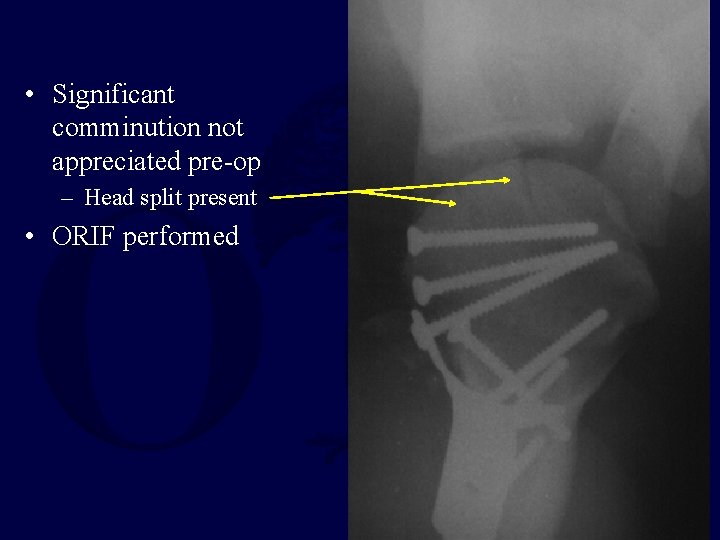

• Significant comminution not appreciated pre-op – Head split present • ORIF performed